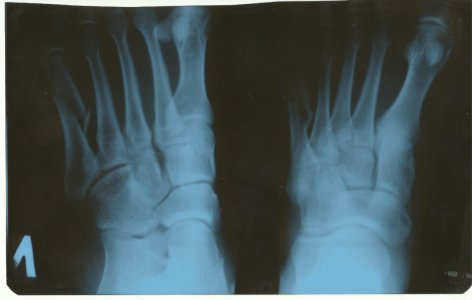

Многооскольчатый открытый внутрисуставной перелом дистальной трети правого бедра и проксимальной трети обеих костей правой голени со смещением отломков, разможжение мягких тканей в области правого коленного сустава(IО-3-4 gj Muller)Закрытый перелом таранной кости правой стопы со смещением отломков.Осл. постравматическая анемия, невропатия нервных стволов голени, посттравматическая аклюзия правой передней б/берцовой артерии. Жду ответа с нетерпением.

Конкретно ответить не могу, не видя ребенка, но так быывает. Возможно само пройдет. К врачу.У сына (13 лет) был перелом 3 и 4 плюсневых костей без смещения. На 24 дня наложили лангету, которую сняли 2 дня назад. Сейчас не наступает на пятку, говорит, что очень больно, и костыль не бросает. А сегодня поскользнулся и сильно наступил на всю стопу, после этого нога болит и в состоянии покоя. В области перелома боли нет. Врач из процедур рекомендовал только ванночки с морской солью. Подскажите является ли это обычной реакцией после снятия гипса и что можно порекомендовать в данном конкретном случае.